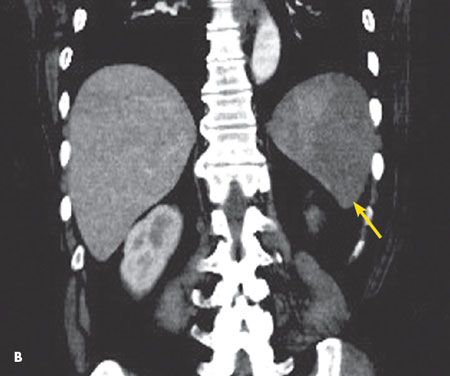

An abdominal CT scan revealed a focal, 5-cm, wedge-shaped area of decreased density in the anterior aspect of the spleen in axial view (A, arrow) and coronal view (B, arrow). This finding is consistent with splenic infarction.